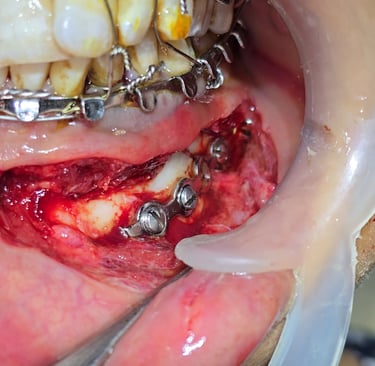

Definitive Surgical Management with Open Reduction and Internal Fixation (ORIF)

Reduction of fractured segments under general anesthesia.

Plating with mini-plates and screws in parasymphysis and angle regions.

Condylar and coronoid fractures aligned with supportive stabilization.

Wound closure was done with proper suturing technique.